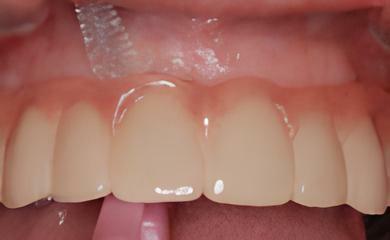

IMPLANTOLOGIE: LES IMPLANTS DANS LE SECTEUR ESTHÉTIQUE